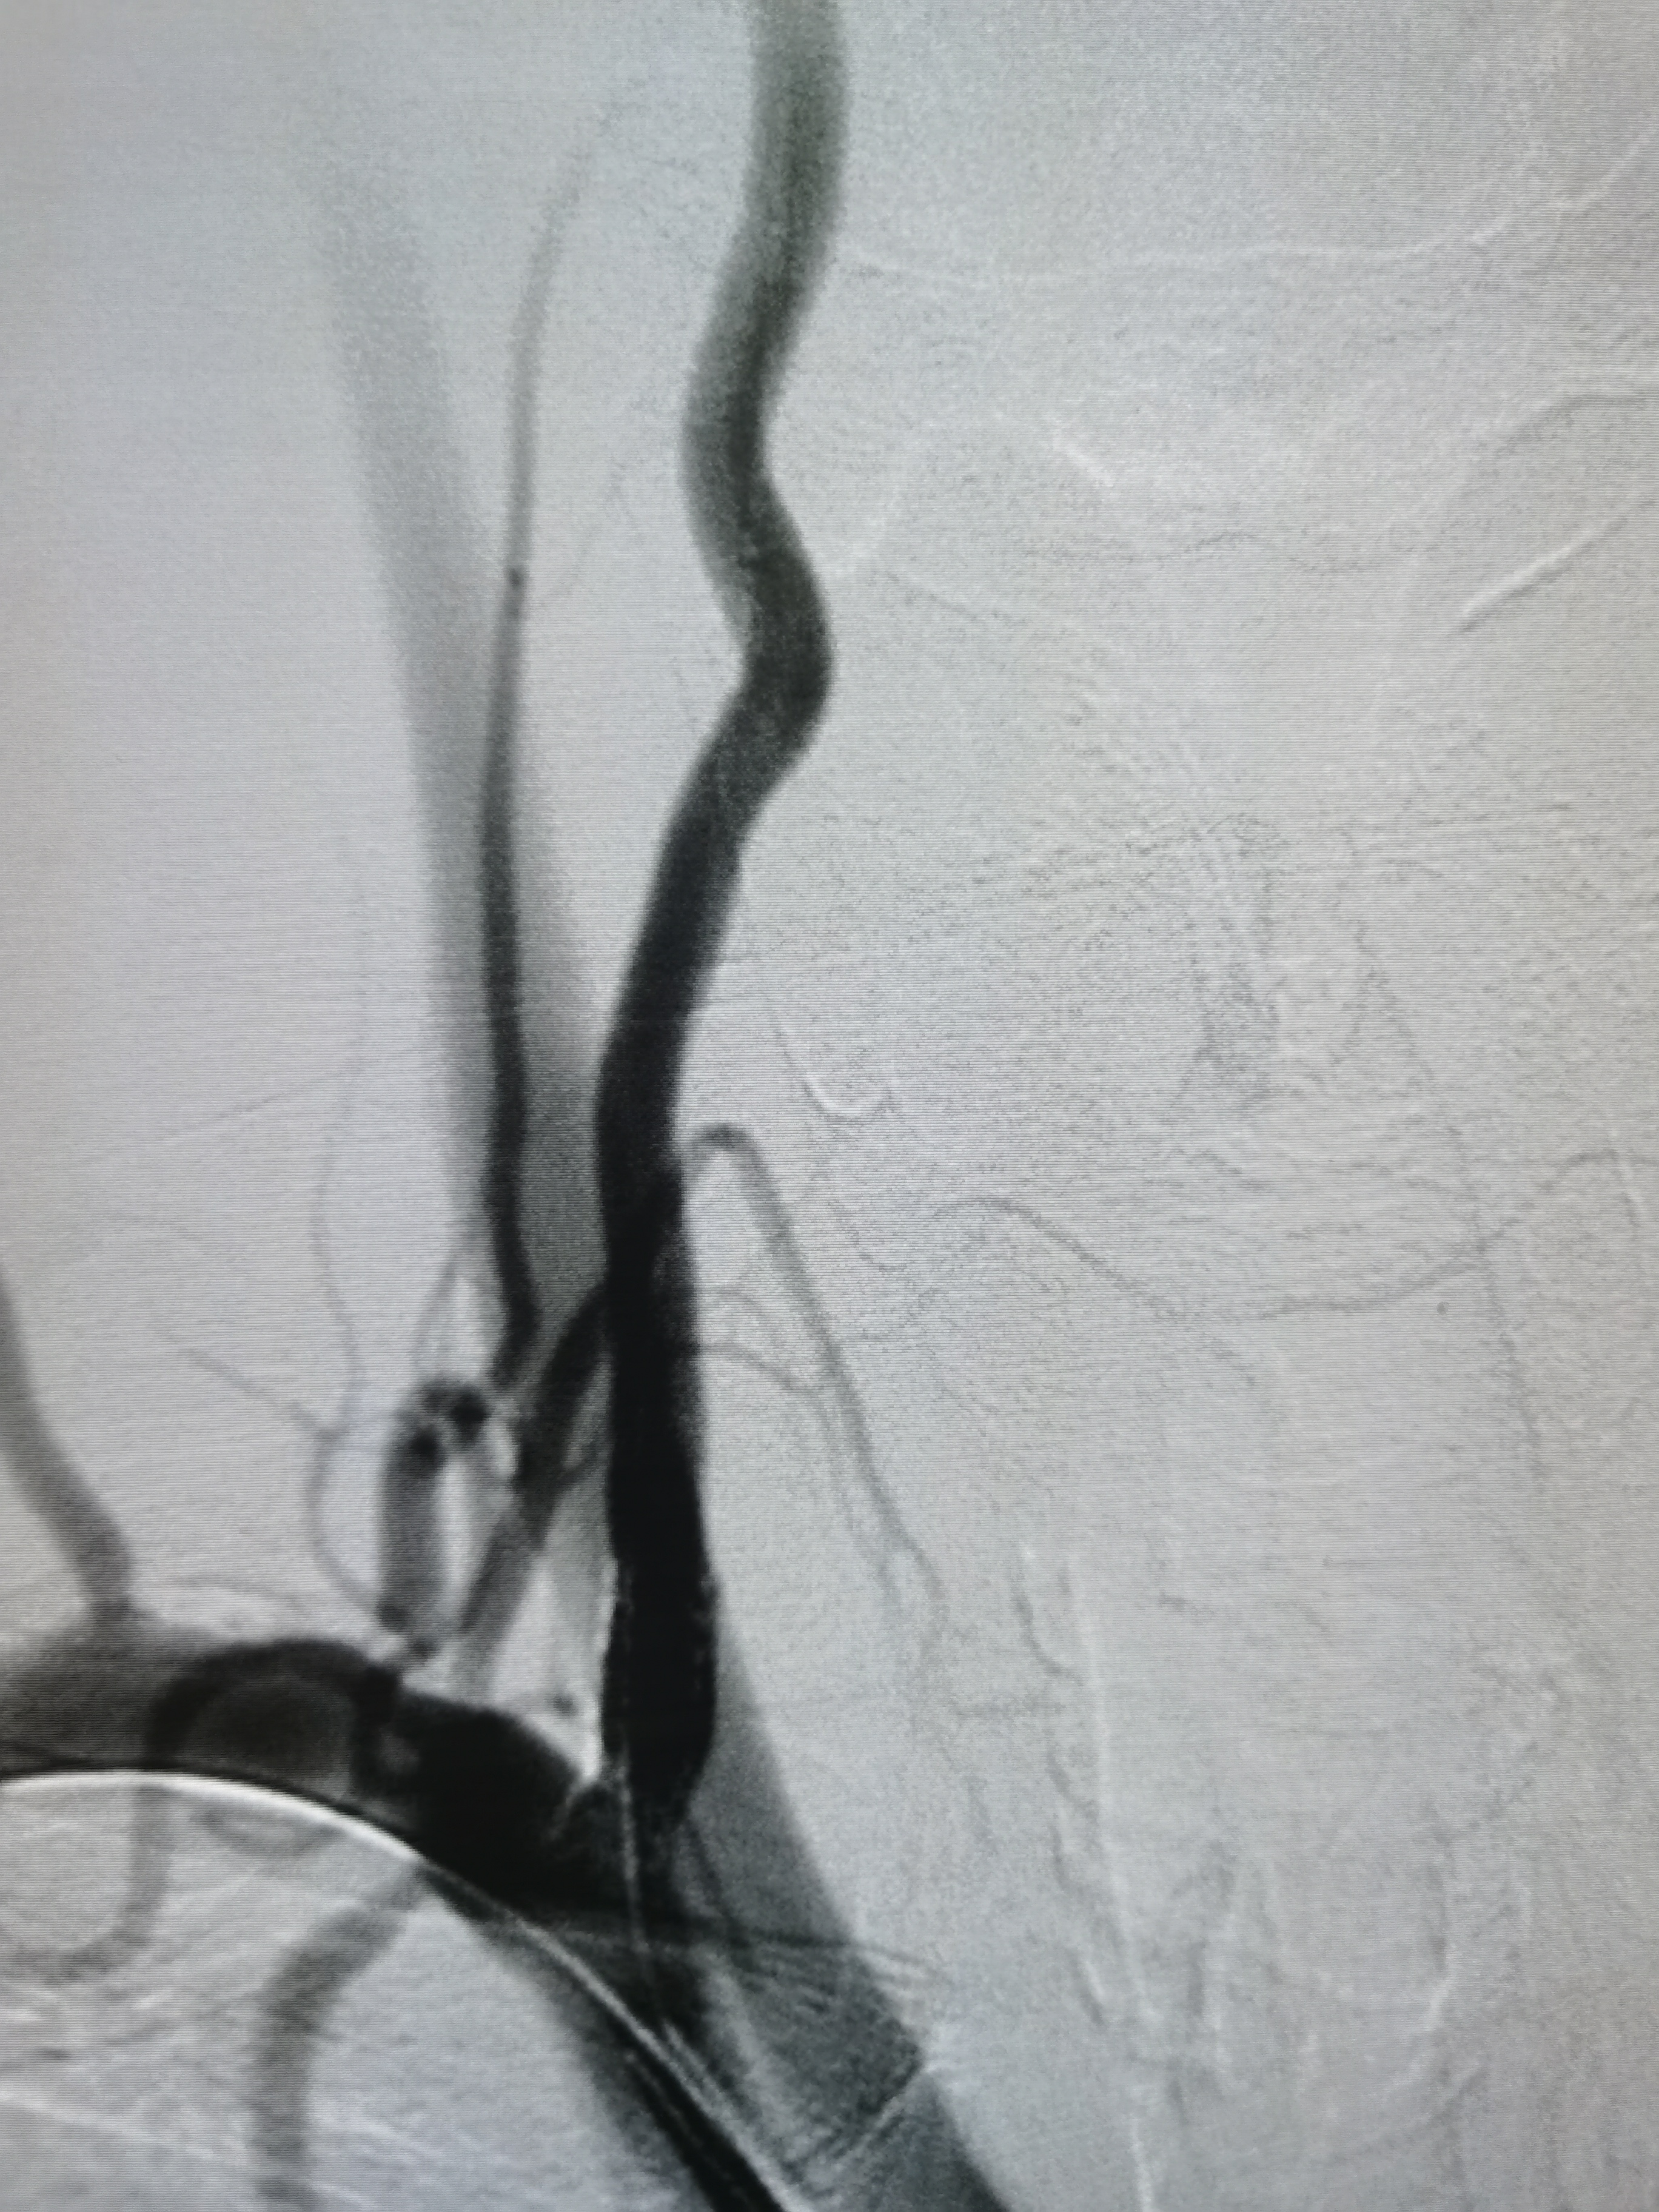

右颈内动脉窦部重度狭窄,局部斑块不稳定。

2、右椎动脉起始部极重度狭窄,系责任血管。

3、右侧颈内动脉起始部重度狭窄,局部斑块不稳定,且右侧后交通动脉开放。

术前术后对比